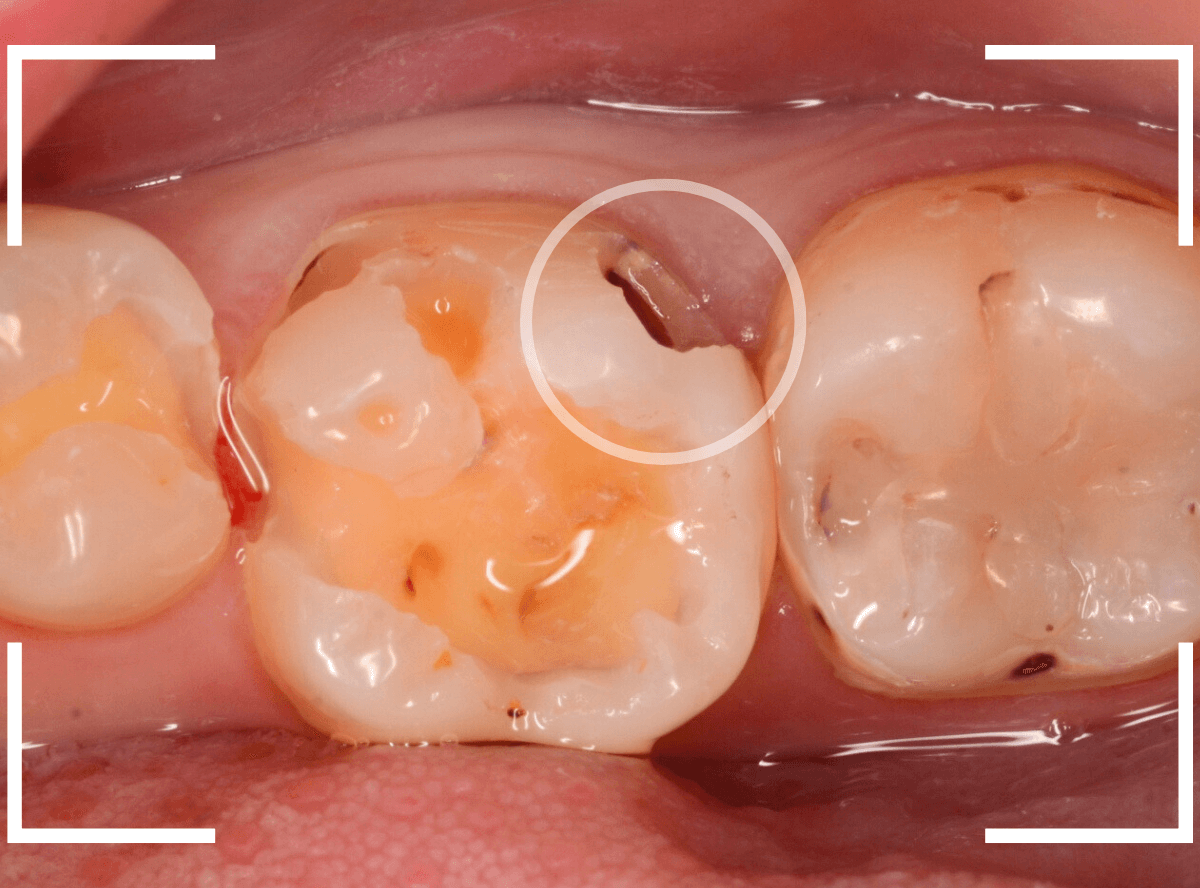

Case.14 噛むと上の奥歯が痛い

「噛むと上の奥歯が痛い」という症状で来院された患者さんです。

打診(ピンセットなどで歯を叩き比べて、痛みの原因の歯を診断する方法)で矢印の歯が痛い事がわかりました。

レントゲン写真で確認します。

レジンの下の赤い色の線が虫歯であろうと思われる部分です。

痛みのある歯については、なんとも微妙な写り方に見え、虫歯だと断言し難い状況でした。

このような場合は、症状とレントゲン写真などから推察していくのですが、痛みは噛んだ時のみで、虫歯特有のしみるなどの症状がないため、そこからも判断しづらい状況でした。

あとは、虫歯と思われる部分を削りながら調べていくしかありません。

患者さんに状況をお話しし、レジンを除去して調べてみると、診断通り、虫歯が出てきました。

虫歯をある程度除去したところです。

まず、一番左の〇部、隣の銀歯との間になにか固いものがはさまっています。

物を噛んだ時に痛むのはこれが原因の気がします。

中央の〇部、赤く染まっている部分は虫歯がまだ除去しきれていない部分です。思ったよりも深めの虫歯です。

一番右の〇部は、メタル・インレーのつけ根に虫歯が小さく顔を出しています。

痛みのある歯の虫歯をすべて除去し、はさまっていた物も全て除去したところです。

手前の歯のメタル・インレーを除去し、虫歯を除去すると、その手前の歯のレジンも不適合なのが見つかりました。

全ての虫歯を除去したところです。

思っていたよりも広い虫歯でした。

しばらくお薬をつめて、経過観察をします。